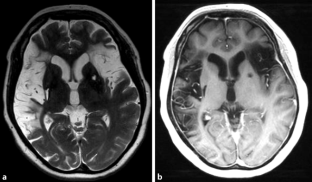

Abb. 4